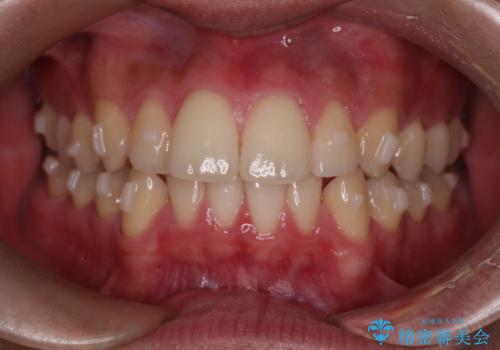

【インビザラインモニター】前歯が出ているのが気になる

- 上の前歯が出ているのが少し気になるとの事で来院されました。

インビザライン希望のため、IPR(歯と歯の間を削る処置)を行うことで、前歯の位置とがたつき整える治療計画を立てました。